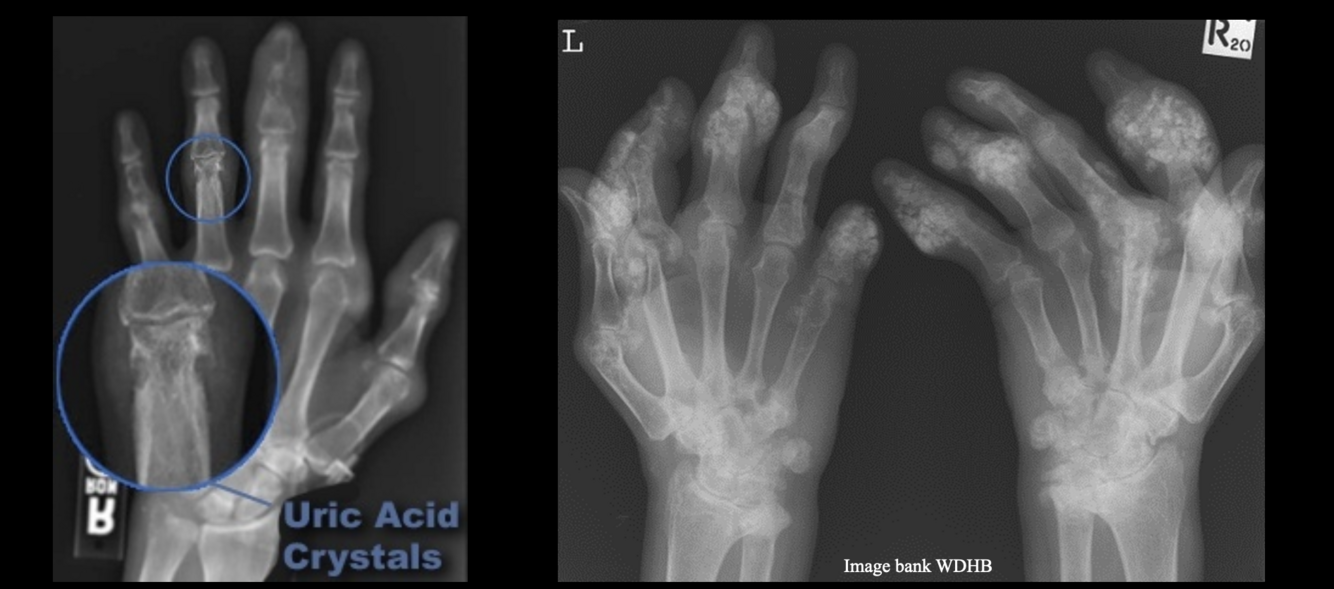

Q

Gout

What is gout indicative of?

Uric acid crystal buildup in the joints due to hyperuricemia.

What are radiographic signs of chronic gout?

Punched-out erosions with overhanging edges (rat-bite lesions), tophi.